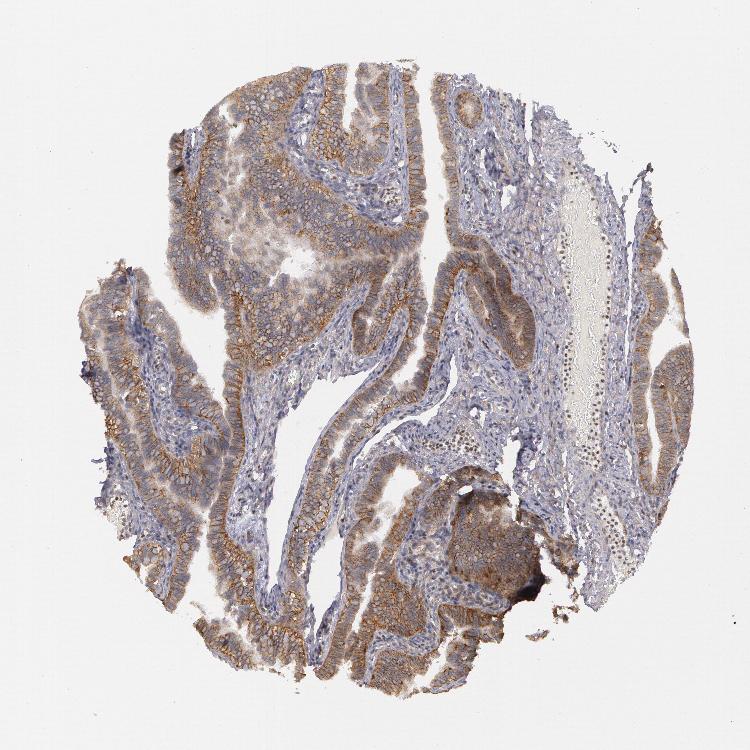

FALLOPIAN TUBE - Antibody stainingi

Antibody staining in the annotated cell types in the current human tissue is reported as not detected, low, medium, or high, based on conventional immunohistochemistry profiling in selected tissues. This score is based on the combination of the staining intensity and fraction of stained cells.

Each image is clickable and will lead to virtual microscopy that enables deeper exploration of all samples and also displays staining intensity scores, fraction scores and subcellular localization as well as patient and tissue information for each sample.

Antibody HPA001383Antibody CAB000043Antibody CAB020416Antibody CAB062555

Glandular cells MediumNot detected-Low